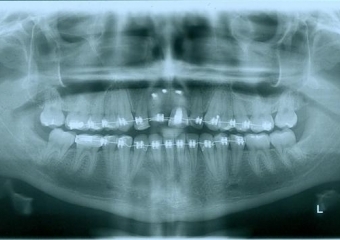

Raio - x Inicial 2013